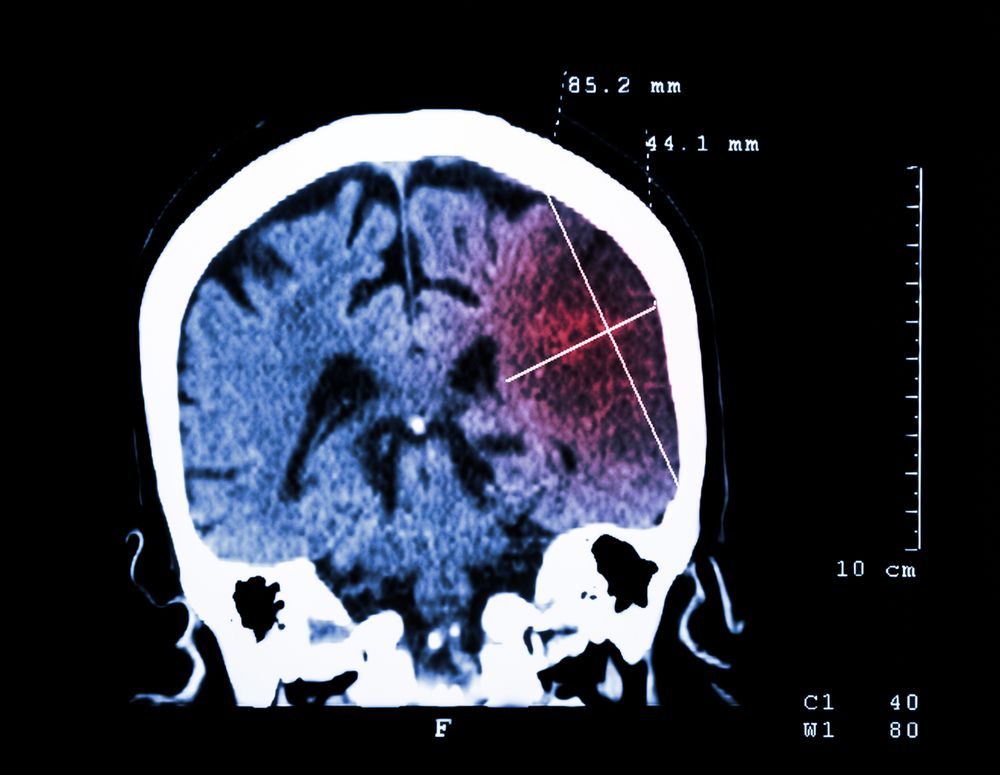

A new study in HIV Medicinehas found that previous or current use of illegal drugs, uncontrolled HIV infection, and some traditional vascular risk factors are associated with ischemic cerebral events in aging people with AIDS.

In a case-control study of 2146 HIV-infected patients followed in the authors’ clinic, those hospitalized between January 2006 and June 2014 with an ischemic stroke or TIA were compared with age-matched and gender-matched controls without stroke.

The study included 20 men and 3 women (mean age 51.3 years) and 23 controls. Among the cases, 83% had had a stroke and 17% a TIA. Small-vessel occlusion was the most frequent etiology, followed by large-artery atherosclerosis, and cardioembolism.

Stroke was statistically significantly associated with diabetes, smoking, and low concentrations of HDL cholesterol as compared with controls. Illegal drug use, a low CD4 count, and a high viral load were also associated with ischemic cerebral events.